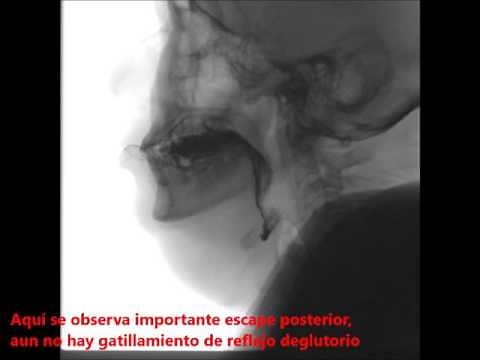

Disfagia videofluoroscopía deglución

27.7K views

May 23, 2016

YouTube

Fonoaudiología Deglución